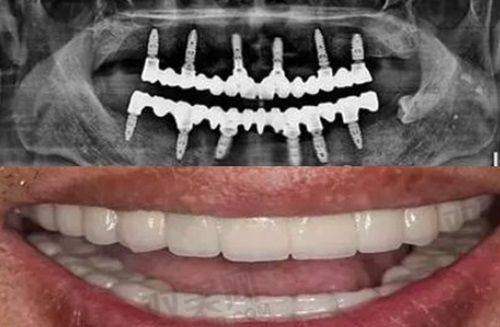

种植义齿并不是真正意义上的种上自然牙齿,而是通过外科手术的方式将人工牙根(种植体)植入缺牙区的牙槽骨内,经过一段时间(通常为3 - 6个月),使种植体与牙槽骨形成牢固的骨结合,然后安装基台、牙冠,从而修复牙齿的形态和功能。它就像给缺失牙齿的部位重新“建造”了一颗新牙,在外观和功能上都与自然牙十分接近。与传统假牙相比,种植义齿具有稳定性好、咀嚼效率高、不损伤邻牙等优点。

全口牙缺失的患者面临着更为严峻的问题,传统假牙在稳定性和咀嚼效率上往往难以满足需求。种植义齿对于全口牙缺失患者来说,是一种革命性的解决方案。可以通过种植4 - 8颗种植体,采用全口种植固定义齿或全口种植覆盖义齿的方式,为患者提供牢固的支撑,大大提高咀嚼效率和舒适度。王大爷全口牙缺失多年,佩戴传统假牙总是不舒服,种植义齿让他重新找回了享受美食的乐趣,个体成效存在差异。